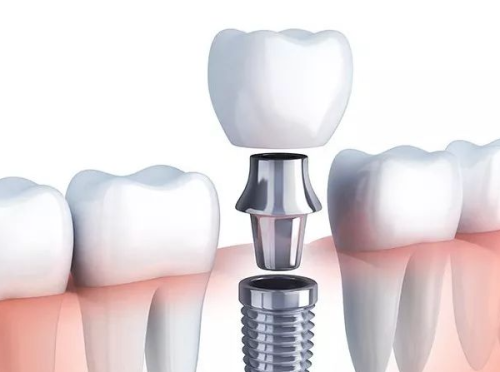

特别多人在考虑种植牙时,都会好奇种植牙5年后真实感受是怎样的。毕竟,牙齿关乎我们的日常生活,从咀嚼食物到展现笑容,都离不开它。今天,我们就来深入探讨一下种植牙5年后的真实体验,为正在犹豫或已经种牙的朋友们提供一些实用的建议。

种植牙5年后真实感受通常是比较正面的,但也存在一些个体差异。大部分患者在功能和美观方面都有不错的体验。不过,要想让种植牙长期稳定地发挥作用,适当的维护和定期的专精检查是必不可少的。

经过5年的使用,大多数患者都能明显感受到种植牙在咀嚼功能上的优势。和传统假牙相比,种植牙非常稳固,功能和自然牙齿特别相似。这意味着患者吃东西时会更加自如、舒适。以前因为牙齿问题不敢吃的苹果、坚果等硬度较高的食物,现在都可以放心食用了。而使用传统假牙时,吃这些食物可能会比较困难,甚至还会有假牙松动的困扰。

种植牙的外观和自然牙齿极为相似,几乎特别难被旁人察觉。这种美观性的提升对患者的自信心有较大的正面影响。拥有美观的笑容,不仅能让患者在社交互动中更加自信,还可能在职业和个人生活中带来积极的影响。想象一下,当你自信地露出灿烂的笑容时,那种感觉是不是特别棒呢?

尽管并发症并不常见,但一些患者在种植牙5年后可能会遇到问题。比如种植体周围炎,这是一种炎症反应,可能会导致种植体周围骨头的丧失。不过,只要定期进行专精检查,就可以及早发现并处理这类问题。另外,长期使用后,部分患者可能需要进行一些小修复,如更换牙冠或紧固松动的零件。这些小问题只要及时处理,一般不会影响种植牙的正常使用。